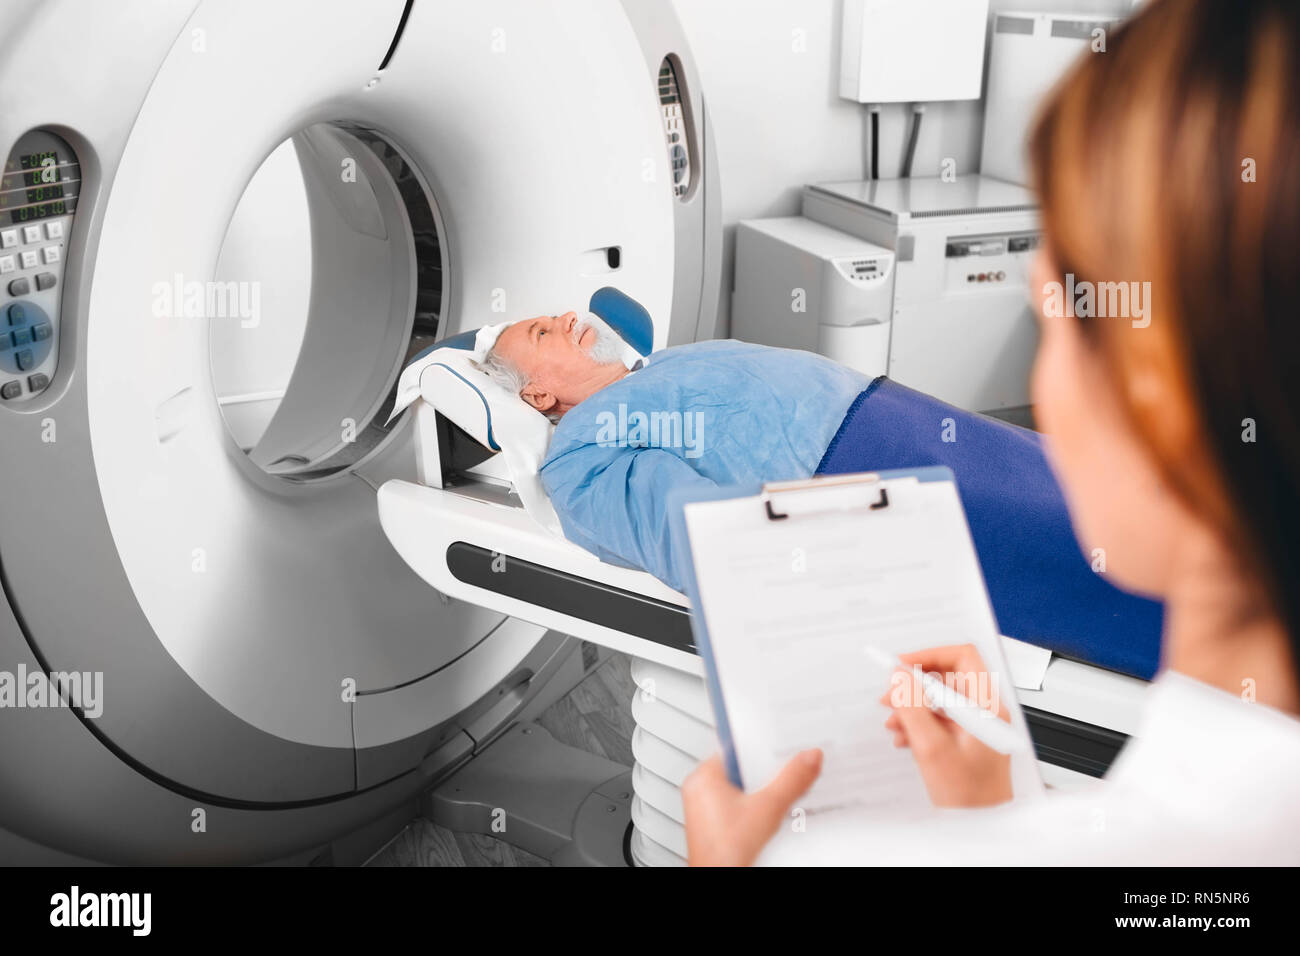

doctor write into medical chart after CT Scan Stock Photohttps://www.alamy.com/image-license-details/?v=1https://www.alamy.com/doctor-write-into-medical-chart-after-ct-scan-image236769434.html

doctor write into medical chart after CT Scan Stock Photohttps://www.alamy.com/image-license-details/?v=1https://www.alamy.com/doctor-write-into-medical-chart-after-ct-scan-image236769434.htmlRFRN5NR6–doctor write into medical chart after CT Scan

Radiologist write into medical chart after CT Scan Stock Photohttps://www.alamy.com/image-license-details/?v=1https://www.alamy.com/radiologist-write-into-medical-chart-after-ct-scan-image240246390.html

Radiologist write into medical chart after CT Scan Stock Photohttps://www.alamy.com/image-license-details/?v=1https://www.alamy.com/radiologist-write-into-medical-chart-after-ct-scan-image240246390.htmlRFRXT4M6–Radiologist write into medical chart after CT Scan